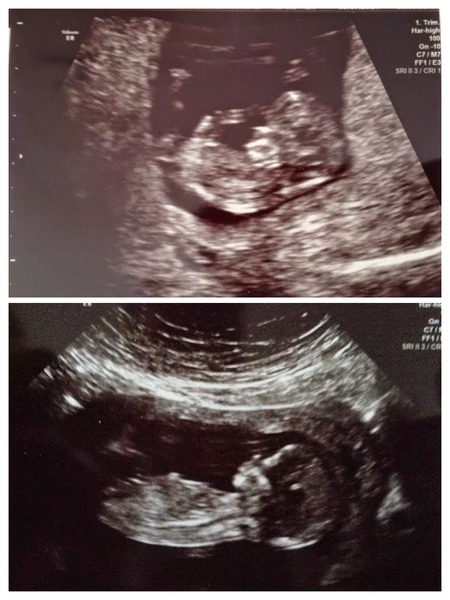

Anyways scan went really well today. Little devil wouldn't get in the right position at all so she had to send me to drink more water. Bit uncomfortable but meant I spent about half an hour looking at the baby! It was all over the place and on it's belly at one point. She said it was very awkward and had made her earn her money!! Also measuring at 13+3, which is unsurprising as I'm 5'10 and DH is 6'4 so we're probably going to have a long one! She said she won't change my due date though. NT measurements were 1.4mm which I think is good?! Results within 10 days. I'll post my comparison scan pics now. Top one is 11 and second 13+1!

Pictures :)

Aww H your scan pics are cuuuute, it's amazing how much they change in only 2 weeks! Smile

H just seen your scan pics as they dont show on my mobile app. They're lovely!!!